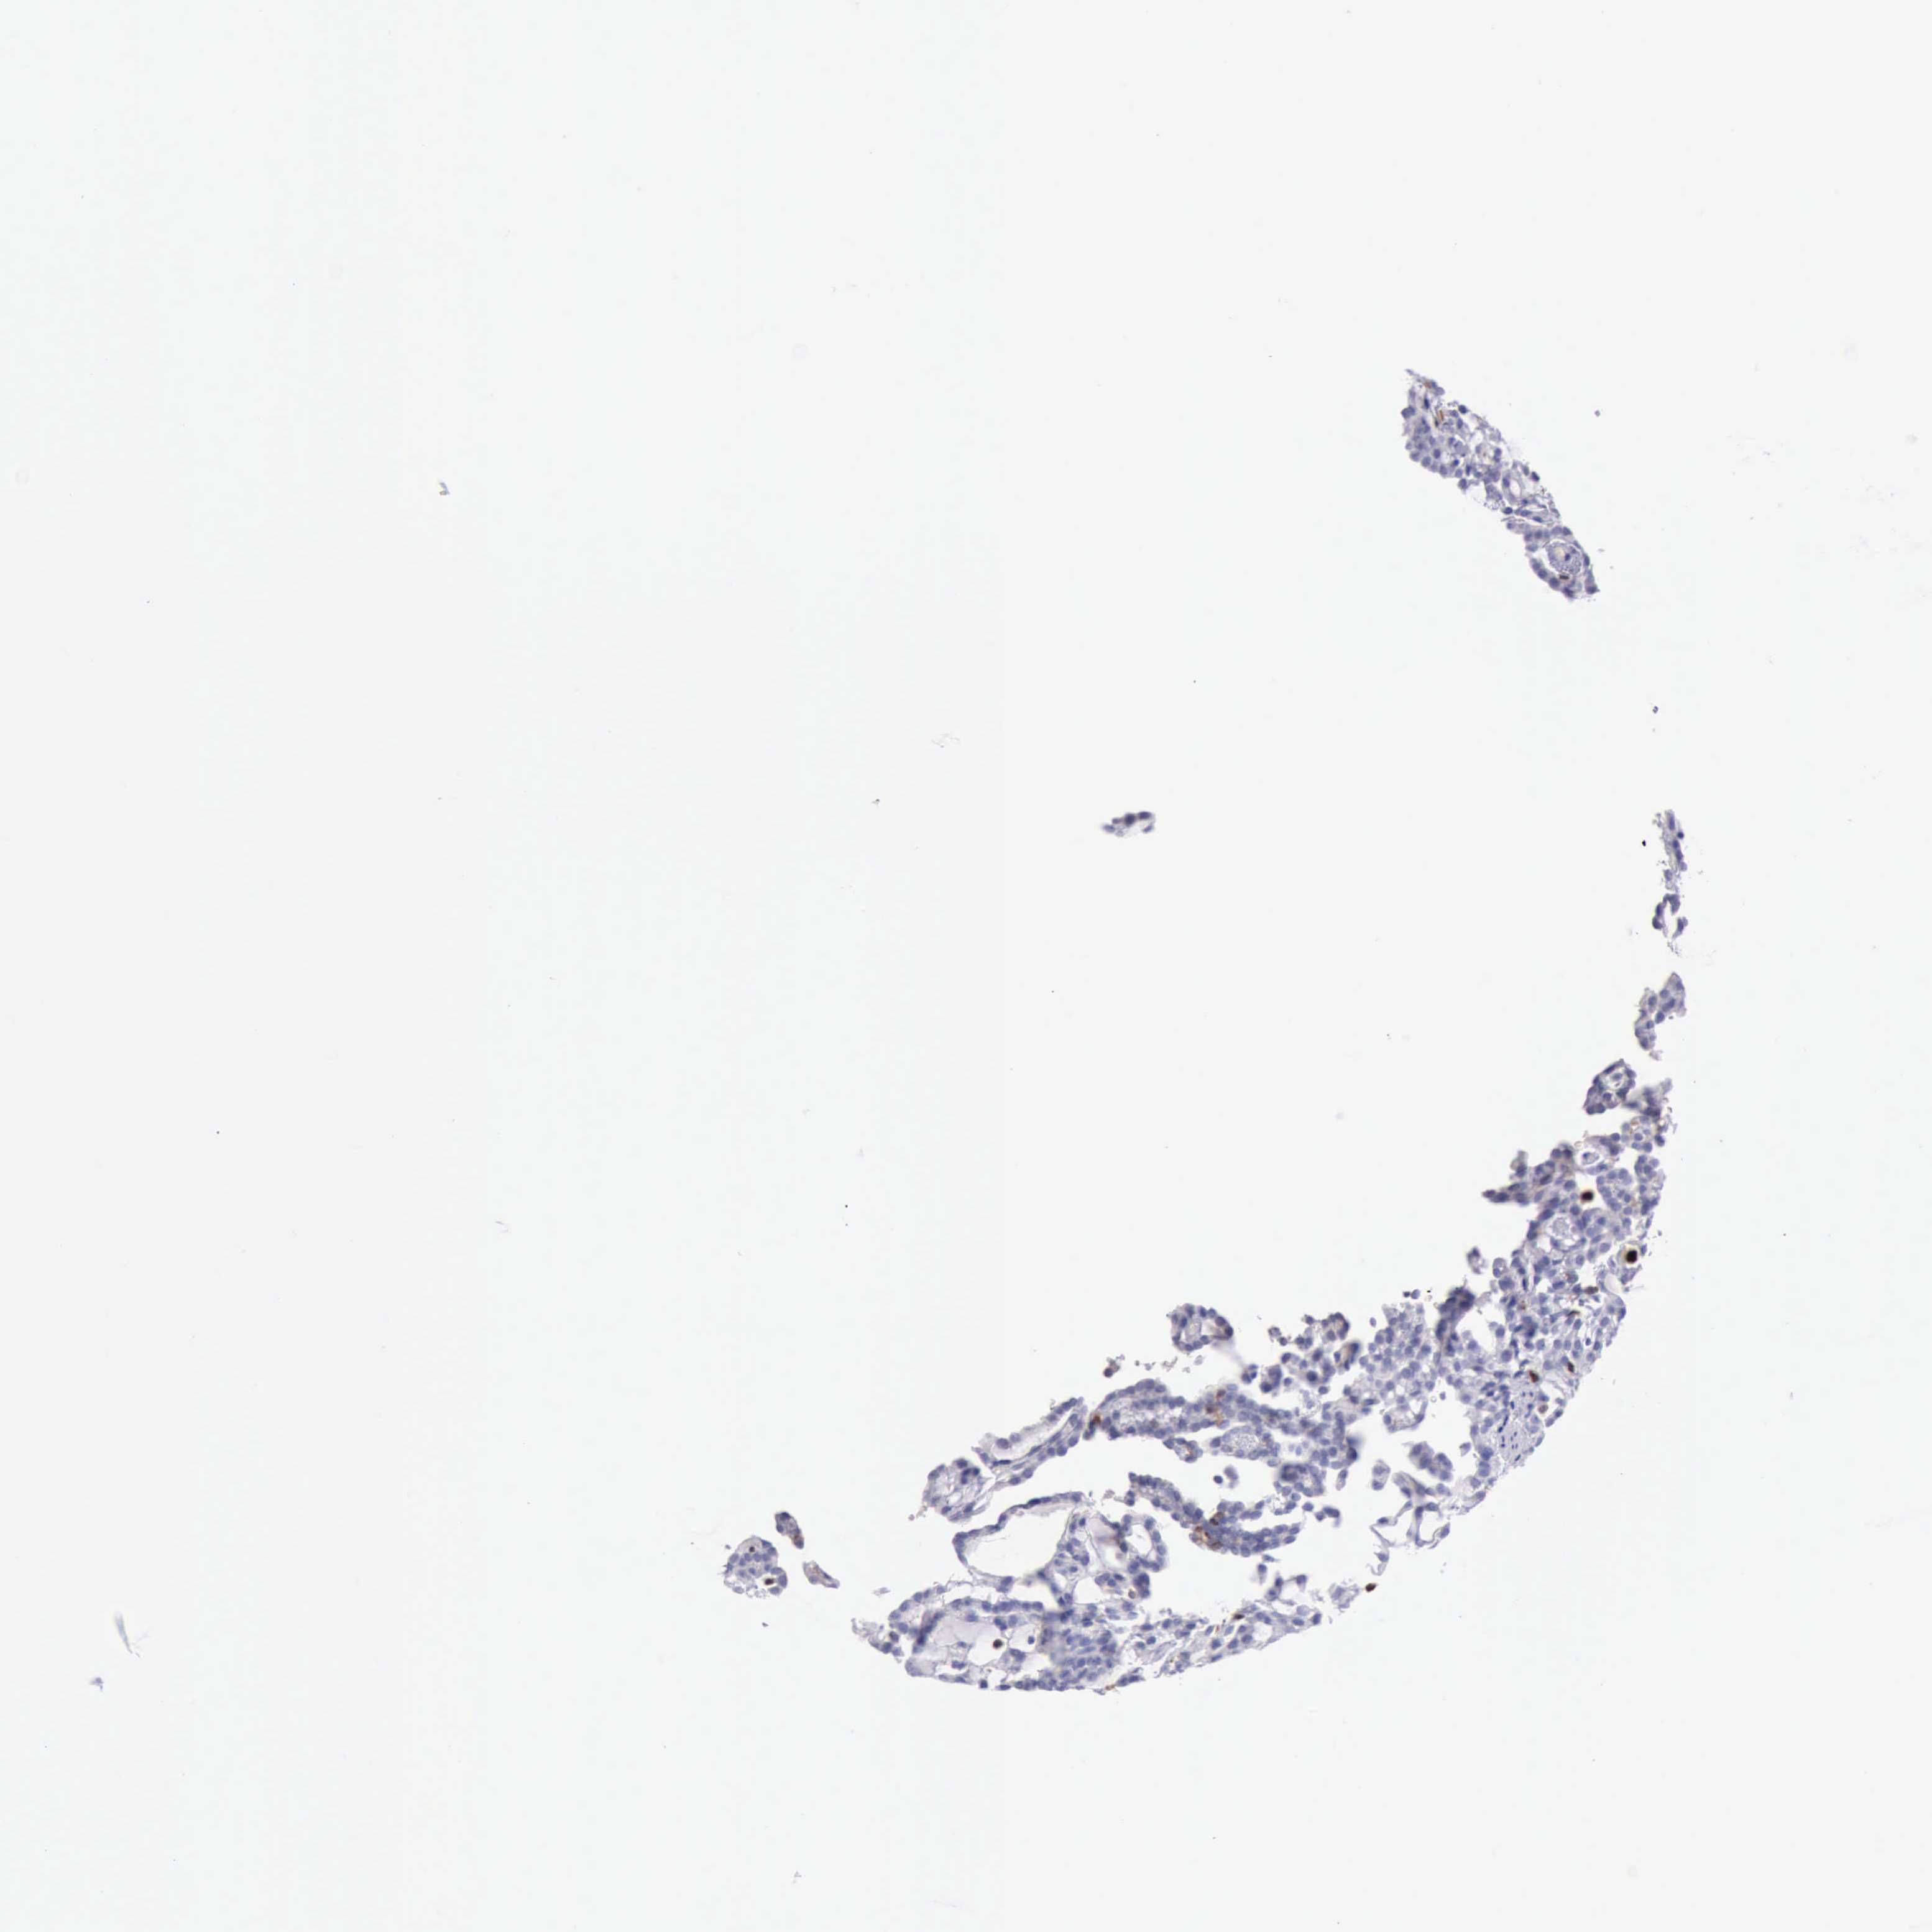

KIDNEY RENAL CLEAR CELL CARCINOMA (VALIDATION) - Interactive survival scatter ploti

The Survival Scatter plot shows the clinical status (i.e. dead or alive) for all individuals in the patient cohort, based on the same data that underlies the corresponding Kaplan-Meier plots. Patients that are alive at last time for follow-up are shown in blue and patients who have died during the study are shown in red.

The x-axis shows the expression levels (FPKM) of the investigated gene in the tumor tissue at the time of diagnosis. The y-axis shows the follow-up time after diagnosis (years). Both axes are complimented with kernel density curves demonstrating the data density over the axes. The top density plot shows the expression levels (FPKM) distribution among dead (red) and alive patients (blue). The right density plot shows the data density of the survived years of dead patients with high and low expression levels respectively, stratified using the cutoff indicated by the vertical dashed line through the Survival Scatter plot. This cutoff is automatically defined based on the FPKM cutoff that minimizes the p-score. The cutoff can be changed by dragging the vertical line or by entering a cutoff value in the square labeled "Current cut-off".

Under the Survival Scatter plot the p-score landscape (black curve; left axis) is shown together with dead median separation (red curve; right axis). Dead median separation is the difference in median mRNA expression between patients who have died with high and low expression, respectively. It is calculated as follows: median FPKM expression of dead patients with high expression - median FPKM expression of dead patients with low expression. This is intended to aid the user in visually exploring custom cutoffs and the associated p-scores and dead median separation.

Individual patient data is displayed and can be filtered by clicking on one or more of the category buttons on the top of the page. Categories describing expression level and patient information include: high, low, alive, dead, female, male and tumor stages. The scale of the x-axis can be toggled between linear and log-scale by clicking on the "x log" button. Mouse-over function shows TCGA ID, patient information and mRNA expression (FPKM) for each patient.

& Survival analysisi

Kaplan-Meier plots summarize results from analysis of correlation between mRNA expression level and patient survival. Patients were divided based on level of expression into one of the two groups "low" (under cut off) or "high" (over cut off). X-axis shows time for survival (years) and y-axis shows the probability of survival, where 1.0 corresponds to 100 percent.

CSTA is not prognostic in Kidney Renal Clear Cell Carcinoma (validation)